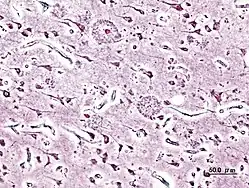

_presenile_onset.jpg.webp)